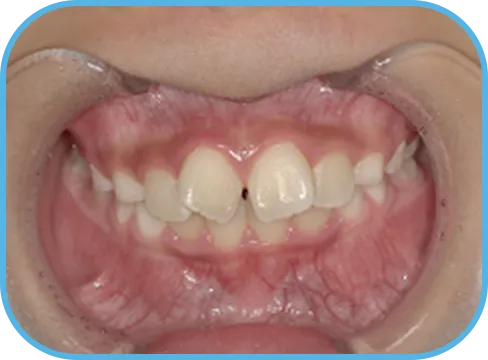

• Before

• 正 面

治療前正面からの歯の様子

• 上 顎

治療前上顎からの歯の様子

• 下 顎

治療前下顎からの歯の様子

• 右 側

治療前右側からの歯の様子

• 左 側

治療前左側からの歯の様子

主 訴

前歯が開いている

治療内容

インビザライン・ファースト

治療期間

6か月

治療費(税別)

450,000円+診断料30,000円

リスク・副作用

• 親知らずの影響や加齢などによって、凸凹が生じる可能性があります。

• 治療の初期段階では痛みや不快感が生じやすくなりますが、1週間前後で慣れます。

• 顎の成長発育によって、噛み合わせや歯並びが変化する可能性があります。

• 状況により当初予定した治療計画を変更する可能性があります。